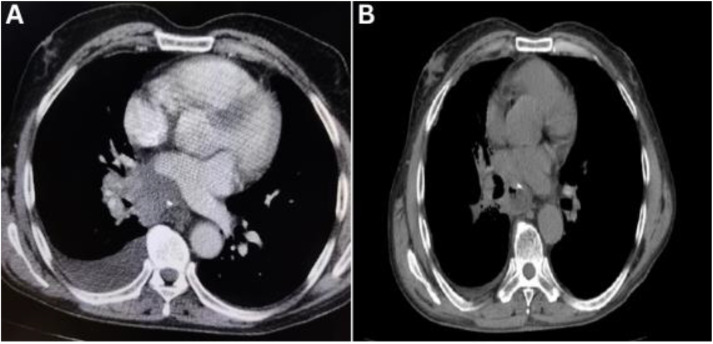

Endobronchial metastases extending to the heart from gastric cancer are rare. This case report describes a 69-year-old man who presented to a tertiary care hospital in Shahrekord, Iran, in 2022 with a history of cough and haemoptysis. He had previously undergone total gastrectomy and adjuvant chemotherapy for gastric adenocarcinoma three years earlier. Imaging and pathological evaluation confirmed endobronchial metastasis with extension to the left atrium. The patient responded well to chemoradiotherapy, maintaining a good quality of life.